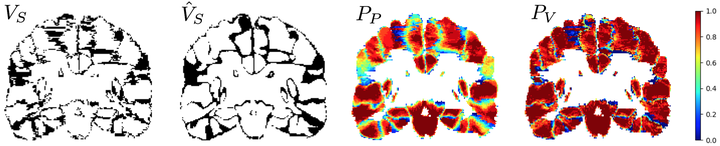

VoteNet is a deep-learning-based label fusion strategy for multi-atlas segmentation (MAS) which locally selects a set of reliable atlases whose labels are then fused via plurality voting. By selecting a good initial atlas set MAS with VoteNet significantly outperforms a number of other label fusion strategies as well as a direct deep-learning (DL) segmentation approach. VoteNet makes use of a fast DL registration approach.